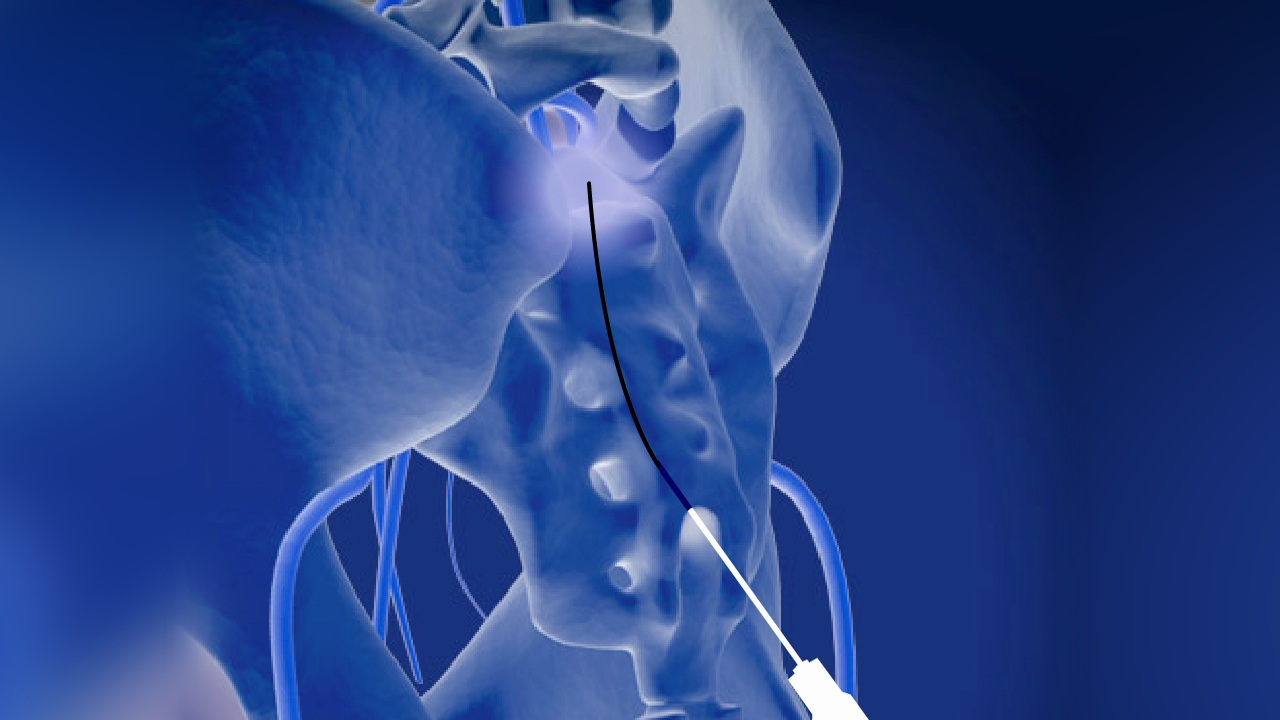

Epiduroplasty and epidural adhesiolysis are minimally invasive procedures designed to break down or dissolve this scar tissue. By targeting this scar tissue, the goal is to free compressed nerves and improve medication delivery , which may provide pain relief.

A catheter is guided to the affected area, lasting 30–60 minutes.

A catheter is guided to the affected area, lasting 30–60 minutes.